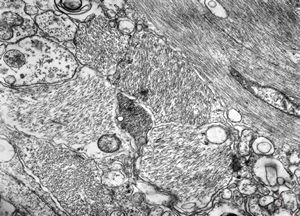

F,50y. | progressive multifocal leukoencephalopathy- viral particles in a glial cell